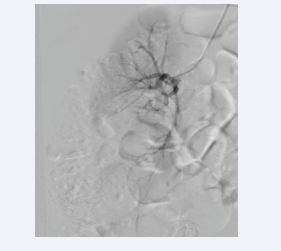

Glue (n-butyl-2- cyanoacrylate) and lipiodol combination were used for embolization (Figure 5).

Embolization.

Figure 5: Embolization.

Embolization successfully performed and post procedure period was uneventful.